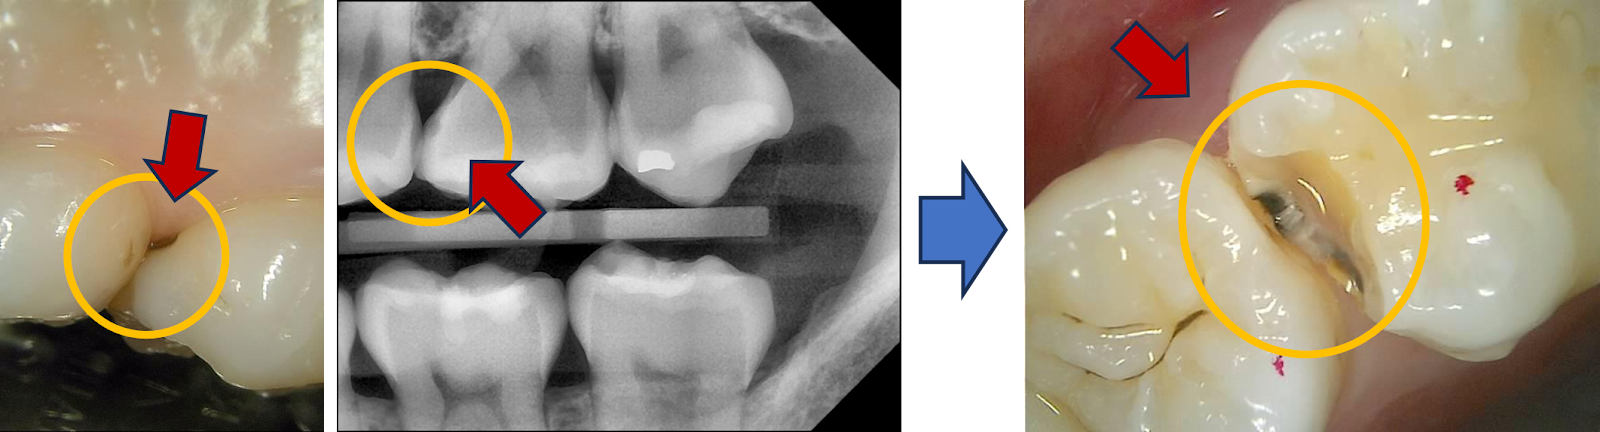

일단, 육안으로 봐도 검게 비치는 부분이 확인되는데

눈으로도 보이는 인접면 충치 진단

CT로 보면 그 심각성이 적나라하게 드러난다.

CT로 인접면 충치 진단

법랑질은 이미 파괴된지 오래고, 상아질 깊게 신경 근처까지 진행된 충치..

그래도 교합면은 양호해서, 다행히 인접면 레진으로도 치료가 가능해보인다.